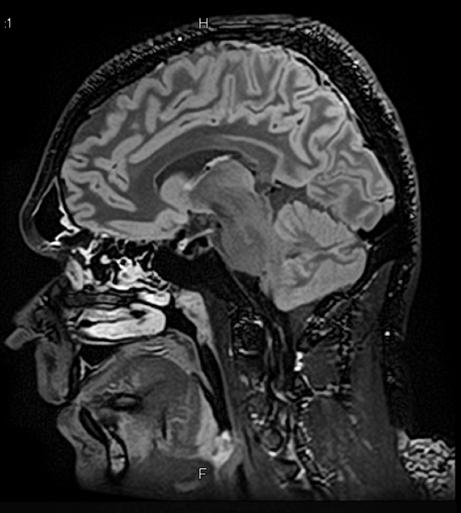

3D FLAIR with DLR. 3D FLAIR Original image. 100s, 0.5x0.5x0.6mm reconstructed

out losing time or signal. The second advantage is the reduction of image acquisition time, as we care less about the signal quality because the noise can be eleminated following the scan,” Prof. Dousset said.

In particular DLR has an important clinical impact in anatomical regions that require a very high resolution, for example parts of the hippocampus and the claustrum.

“The DLR brings a spatial resolution that I have never seen before in neurologic imaging. I recently pointed out a brain area, for example the claustrum, that is almost invisible on standard MRI images even with very high resolution or high field devices. However, thanks

to the DLR we could highlight this kind of brain anatomy. So, indeed, there is a considerable advantage to using this technique.” Prof. Dousset said.

Prof. Tourdias worked at 7T to visualise extremely fine structures of the hippocampus while at Stanford. With DLR, he can now do this task with a 3T. “When we compared the images we realized that by pushing the 3T machine and processing with DLR that we were able to achieve a similar result to what we could achieve with 7T. I think this is the main surprise of the technology.” he said.